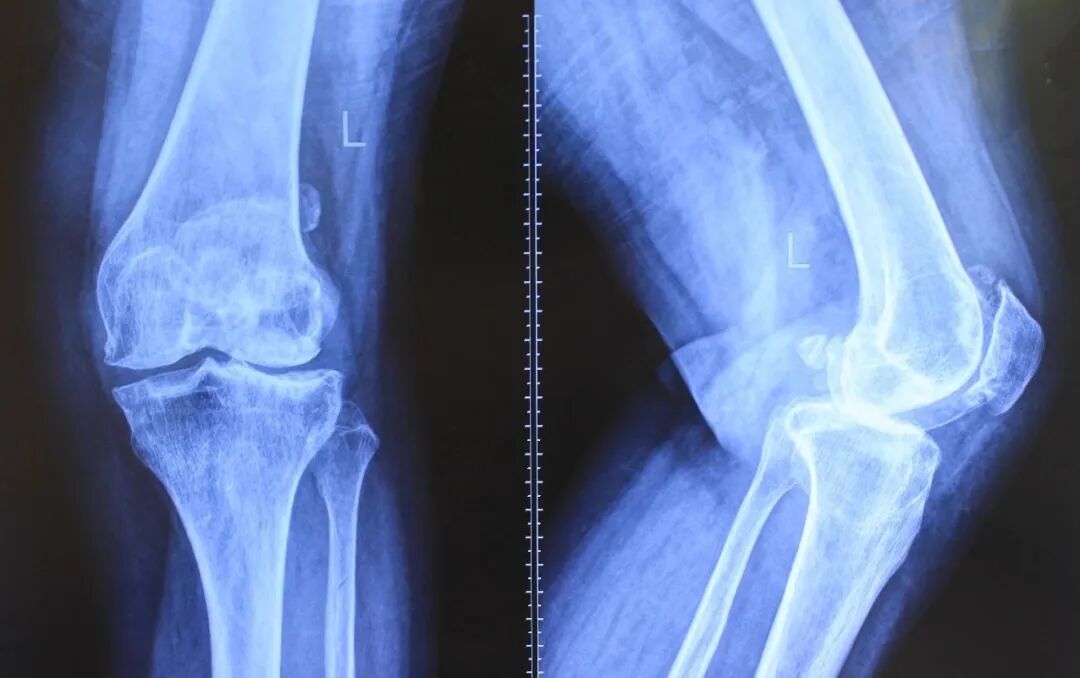

膝关节包括骨头、韧带、关节腔和半月板、软骨,上接大腿骨(股骨),下接小腿骨(胫骨)。当我们走动时,就牵动大、小腿骨的运动造成膝关节磨擦,而靠软骨和关节液来减少摩擦。

可以说一旦出现关节变形的情况,保守治疗效果就会很差,甚至完全无效,患者会长期持续忍受关节疼痛的痛苦,让最简单的走路变得非常艰难!